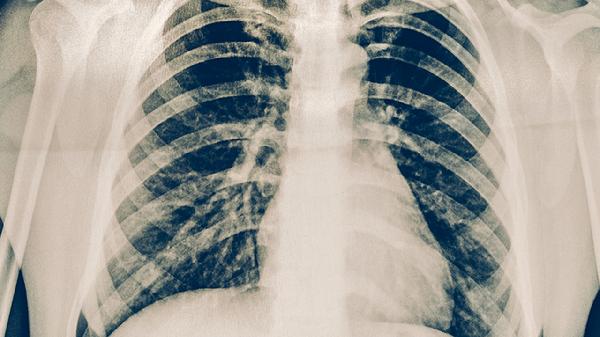

肺结核治愈后若肺部病灶完全吸收或仅遗留稳定钙化灶,无传染性及功能障碍,体检通常不受影响。这类患者需提供既往治疗记录和近期胸部影像学复查报告,证明疾病已临床治愈。部分患者可能因陈旧性纤维灶导致肺功能轻度下降,但未超过体检标准阈值时仍可合格。

存在活动性结核病变、广泛肺纤维化伴明显通气功能障碍,或合并支气管扩张等并发症时,体检可能判定不合格。特殊职业如食品加工、幼教等行业对呼吸道传染病史要求更严格,即使治愈后也可能受限。未经规范治疗或自行停药者,需完成全程抗结核治疗并复查确认病灶稳定。